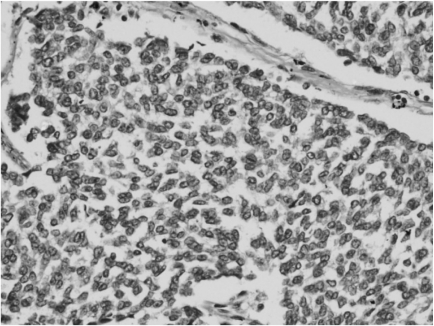

Figure 4

Section shows sheets of small round tumor cells with a rim of clear cytoplasm (H&E, × 400).